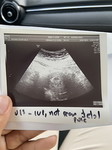

กำหนดคลอด4มีนาค่ะ หมอบอกน้องกลับหัวแล้วค่ะ ภาวนาให้รีบออกมาแล้วค่ะ

บ้านนี้27มีนาค่ะ.หมอนัดวันที่5ไปซาวดูรกแล้วดูว่ากลับหัวหรือยังค่ะ

คุณหมอนัดผ่าที่37weekค่ะ 5/3/67 ตอนนี้ตัวเลข หนัก 2.6 โลละค่ะ